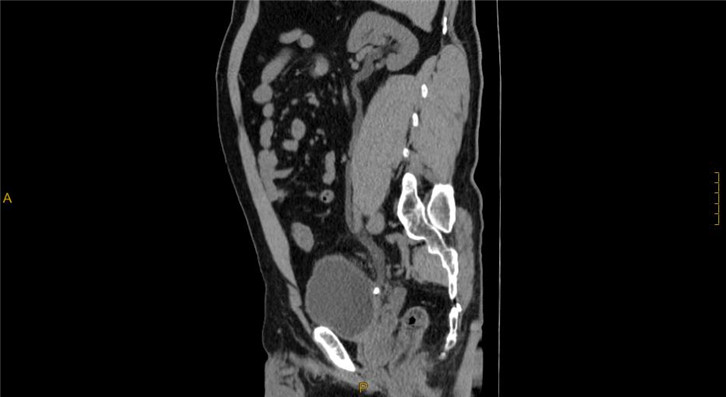

·Comprehensive 32 slices spectral imaging platform enables hospitals at all levels to enjoy the advanced functions of super high-end CT. Spectral imaging platform has rich clinical value in stone composition analysis, gout examination and tumor examination

Clinical Gallery